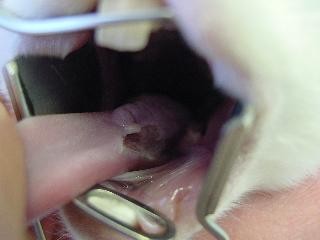

Choroby zebów u królikaW przychodni lekarz obejrzy najpierw głowę i szczękę , siekacze i zgryz można łatwo sprawdzić podnosząc wargi królika. Specjalnym oświetlonym otoskopem (z metalowa końcówką), można ocenić zęby przedtrzonowe oraz miękkie części np. język, policzki. Przy najmniejszym podejrzeniu anomalii cała jama gębowa powinna zostać dokładnie przebadana. Z powodu dużego zagrożenia urazami podczas badania, powinno być one przeprowadzone pod narkoza. Choroby zebów u królika Tylko podczas znieczulenia ogólnego można przeprowadzić szczegółowe badanie wszystkich miejsc w szczęce. Zdjęcie rentgenowskie przy zamkniętej i otwartej szczęce , pozwoli wykryć szczękowo-ortopedyczne problemy. Poza tym można zobaczyć przerost zębów, czy zmian kości i korzeni spowodowanych ropniem.

Choroby zebów u królikaGłównym celem jest przywrócenie prawidłowego zgryzu siekaczy i zębów trzonowych, tak żeby umożliwić naturalne gryzienie i żucie. Skracanie siekaczy małym zwierzętom domowym jest z reguły możliwe bez użycia narkozy. Aby uniknąć powstawania odłamków/ rys np. aż do korzenia zrezygnujmy z cążek. Do tego lepiej nadają się szybko obracające się wiertła z diamentowa tarcza. Stopień skracania zależy od rodzaju zwierzęcia. U królików siekacze w przeciwieństwie do trzonowych dotykają się ze sobą, dobranie prawidłowej długości nie stanowi problemu. U gryzoni na odwrót. Zęby trzonowe, przy zamkniętej szczęce, dotykają się natomiast siekacze nie maja ze sobą kontaktu. Profesjonalne skracanie zębów trzonowych jest możliwe tylko pod narkoza czy znieczuleniu ogólnym. Choroby zebów u królikaTylko w ten sposób można dokładnie zbadać jamę ustna i po wykonaniu zdjęcia RTG rozpocząć prawidłowe, a dla pacjenta bezpieczne leczenie. Przy zachowaniu dużej ostrożności i ochronie miękkich części, szybko obracającym się instrumentem przeprowadza się korekcje zgryzu. Zdjęcia pokazują zęby przed i po operacji. Nie powinno się do tego celu używać cążków, ani pilników diamentowych, ponieważ ryzyko naruszenia fraktury zęba, czy skaleczenia miękkich części jamy gębowej jest nie do przewidzenia. Podczas przywracania naturalnego zgryzu zwierzakowi, należy pamiętać że powierzchnia gryząca powinna być odchylona o 10°, u świnek morskich o30 ° , a u szynszyli jest prawie horyzontalna. Jeśli nie można uniknąć usunięcia zęba,powinno się po udanej ekstrakcji oczyścić także zębodół. aby zapobiec odrostowi tkanki zęba. W związku z ograniczeniem jakim jest mały otwór gębowy zwierząt, czasami dojście do zęba jest łatwiejsze od zewnętrznej strony. Po usunięciu zęba , ząb przeciwległy ma tendencje do nadmiernego rozrostu, to może doprowadzić do wrośnięcia zęba w puste miejsce. Regularne kontrole i korektura jest nieodzowna.